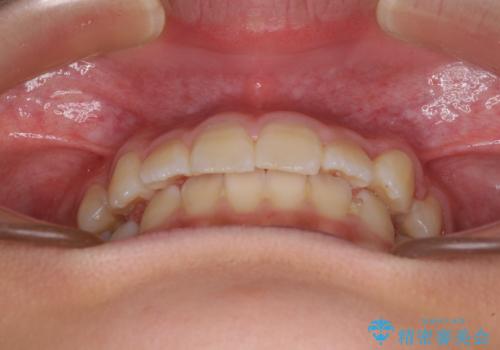

埋もれた犬歯を引っ張り出す 小学生のⅠ期治療

- 小学校での定期歯科検診にて歯列不正を指摘されたとのことで来院された患者様です。

左上の犬歯が低位に埋伏しており、将来八重歯になるリスクが高いと判断されたため、補助装置とワイヤーを用いて犬歯を通常の位置まで移動させることとしました。